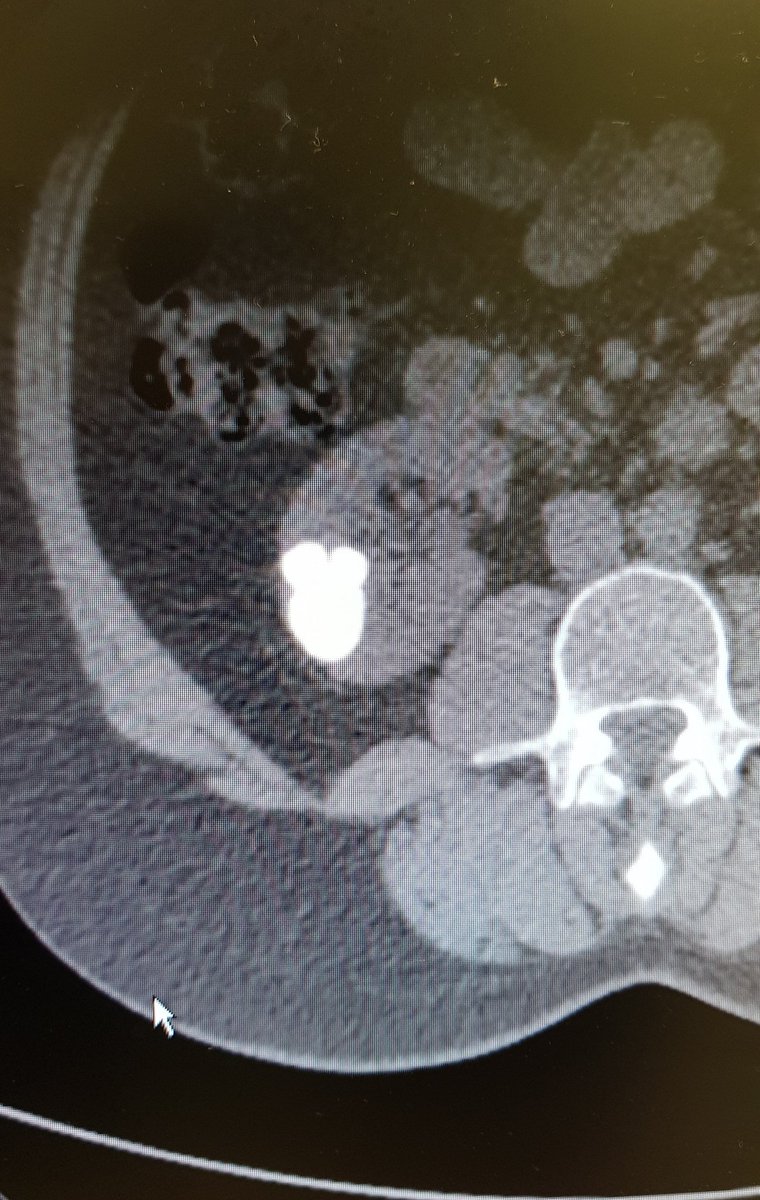

📣 ePub: ProBE-PC study of TR vs TP biopsy complications. 1st RCT ✅ 💪 Tremendous job by the team @AlbanyMedUro @AlbanyMed 🙏 to the 763 patients who volunteered Will discuss details, biases, blind spots @uroonc in 2 wks @AmerUrological #prostate auajournals.org/doi/10.1097/JU…